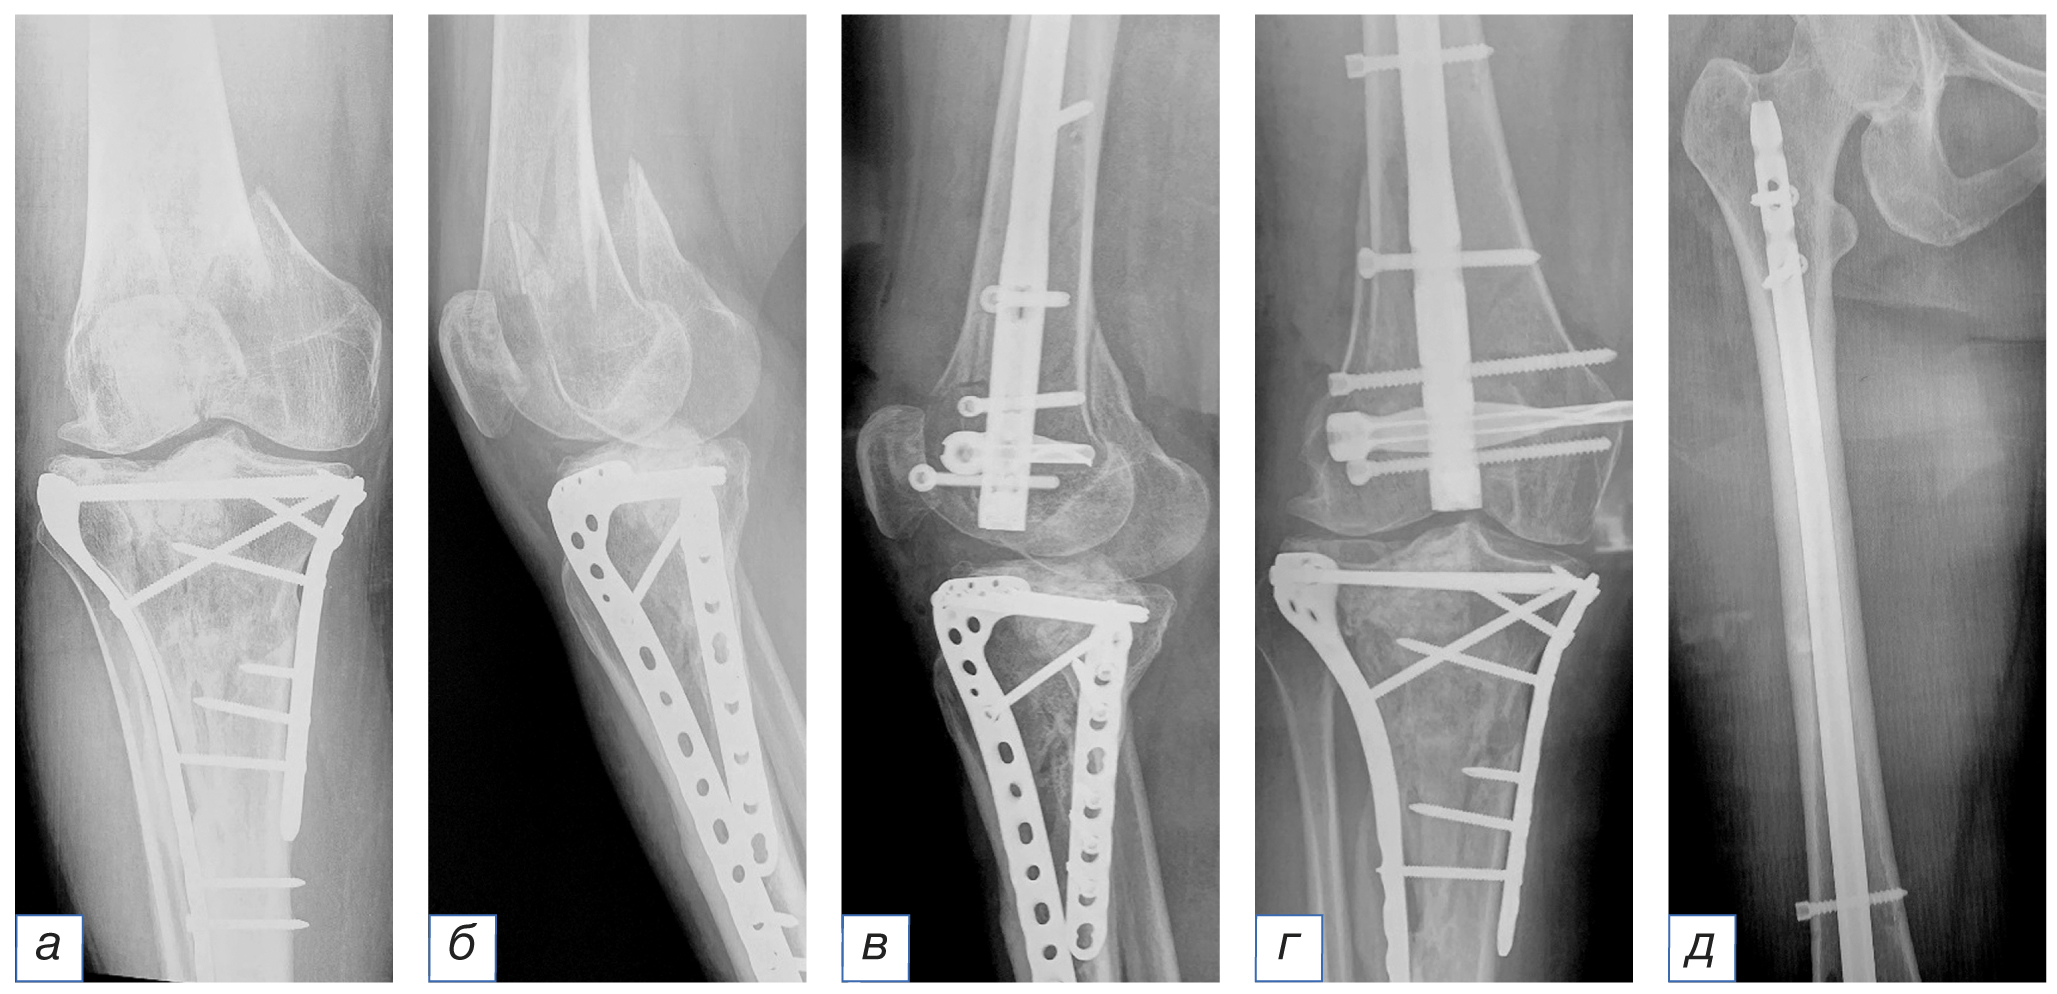

О пациенте. Пациентка В., 62 года. Травма в результате дорожно-транспортного происшествия (пассажир). Диагноз: «Закрытый оскольчатый перелом дистального отдела правой бедренной кости (33С2), сочетанная травма» (рис. 7).

Рис. 7. Рентгенограммы пациентки 62 лет с диагнозом закрытого оскольчатого перелома дистального отдела правой бедренной кости до операции (а) и после оперативного лечения (б–д). / Fig. 7. Radiographs of the 62-year-old patients with a diagnosis of a closed comminuted fracture of the distal right of femoral bone before (а) and after the surgery (б–д).

Из анамнеза: остеосинтез перелома проксимального отдела правой большеберцовой кости двумя пластинами выполнен 5 лет назад.

Обстоятельства травмы. Доставлена в приемное отделение клиники через 28 мин с момента получения автомобильной травмы.

Лечение и прогноз. Госпитализирована в реанимационное отделение с целью проведения противошоковой терапии. После стабилизации общего состояния выполнен ретроградный интрамедуллярный остеосинтез дистального отдела бедренной кости. Послеоперационный период протекал гладко. Послеоперационные раны зажили первичным натяжением. Ходьба с дозированной нагрузкой при помощи костылей разрешена после 2-го дня операции. Через 6 мес после операции угол сгибания в коленном суставе составил 106°, разгибание — полное. Болевых ощущений пациентка не отмечает.